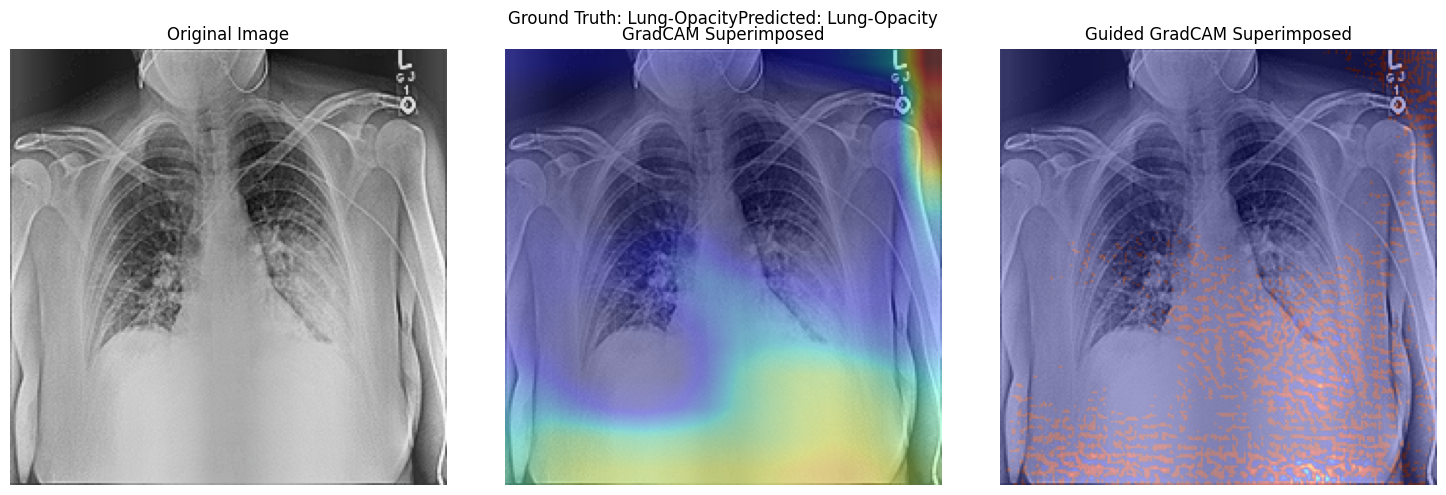

Resnet50 Activation Visualisation Using Grad Cam and Guided Grad Cam.

• Testing Different Alpha Values for super imposition of gradcam heatmap with original image.

• Comparing Original Image with Grad Cam Heatmap Superimposed Image.

Activation Map Visualisation

Research Question 2 and Model Interpretability.

• Research Question 2 : What insights can be derived from activation visualization or attention map visualization about the decision-making process of the pre-trained vgg19, resnet50 models or custom CNN and vision transformer models, respectively, in predicting respiratory diseases from chest radiological images?

• Insights from Activation and Attention Map Visualizations in Chest Radiological Images Classification

• Activation and attention map visualizations offer transparency into neural networks, highlighting areas deemed significant during predictions. Such insights are crucial for medical imaging applications, where the understanding of a model's focus can aid in validation and trust.

• 1. ResNet50:

Using gradient-based visualization, ResNet50 pinpoints distinct chest X-ray features indicative of respiratory diseases, like opacities. However, its attention sometimes extends to noise and image edges. This could be influenced by the zoom preprocessing, emphasizing both critical regions and noise.